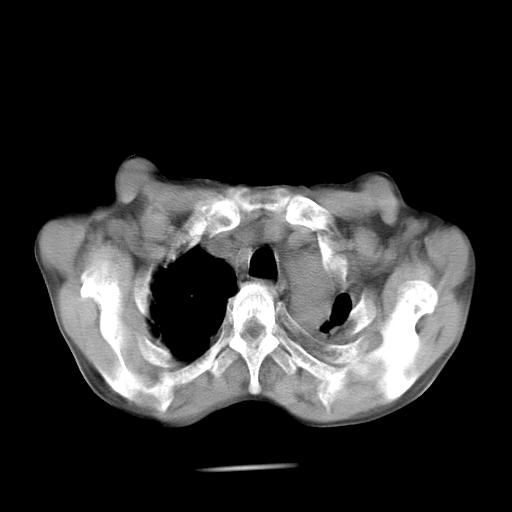

男  70岁,发烧咳嗽4天。盗汗,消瘦。无痰中带血丝,以前有肺tb病史,ct见,双肺tb,左侧胸廓塌陷,左胸膜肥厚粘连。纵隔移位,右侧胸腔积液,大家说说那个心影前左肺舌叶除了肺大炮还有炎症还是干酪性肺炎?有占位吗?我看纵隔淋巴结也大。

双肺继发性肺结核伴部分左肺毁损!

1)两肺继发性肺结核并左肺上叶肺不张,支气管扩张。2)双侧胸膜炎(胸膜增厚+少量胸腔积液)。